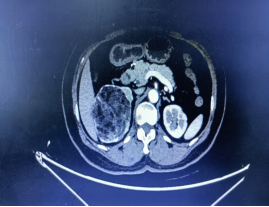

年近6旬的张女士(化名),近期在常规体检中发现右肾存在占位性病变,进一步检查后确诊为右肾多发肿瘤:最小直径约1cm,最大直径约8cm!尽管术前检查考虑良性可能,但由于患者肾脏肿瘤多发,保肾难度大,且对侧肾功能良好,术前检查无禁忌症,医生最终为她实施了全麻下腹腔镜右肾切除手术,张女士(化名)遗憾地失去一颗宝贵的肾脏。

术前影像